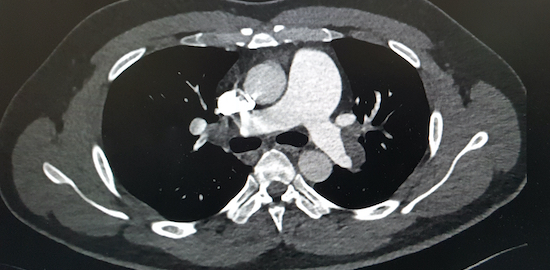

Originalstudie Kan val av röntgenmetod förklara den stora skillnaden i incidens mellan Region Dalarna och Region Värmland?